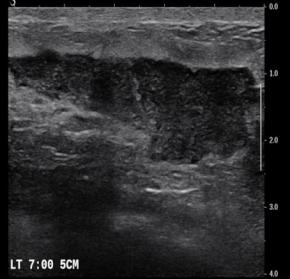

[Breast] 35 /F, Palpable mass, left with redness

Diagnosis Idiopathic granulomatous mastitis

Comments Idiopathic granulomatous mastitis (IGM) is a rare benign inflammatory breast entity characterized by lobulocentric granulomas. IGM has a persistent or recurrent disease course and affects parous premenopausal women with a history of lactation. It has also been associated with hyperprolactinemia. The most common clinical sign is a palpable tender mass. However, the nonspecific manifestations and varied demographic features of this condition, as well as the other similar-appearing and superimposed breast entities, pose substantial diagnostic challenges. Entities with similar manifestations include inflammatory breast cancer (IBC), infective mastitis, foreign body injection granulomas, mammary duct ectasia, diabetic fibrous mastopathy, and systemic granulomatous processes. The strategy for imaging IGM depends on patient age, clinical manifestations, and risk factors. Targeted ultrasonography, mammography, and less commonly, magnetic resonance imaging have proven to be useful for imaging evaluation. Core-needle biopsy, with or without fine-needle aspiration for cytopathologic examination, and culture analysis are usually required to exclude IBC and other benign inflammatory breast processes. Patients with IGM have an excellent prognosis when they are appropriately treated with oral steroids or second-line immunosuppressive and prolactin-lowering medications. However, surgical excision may be an option for patients in whom medication therapy is unsuccessful. Imaging surveillance can be offered to patients with incidentally encountered IGM or mild symptoms. Clinical suspicion for this rare disease and the breast imager’s prompt diagnosis can lead to an improved patient outcome. The purpose of this article is to review the imaging manifestations of IGM in a multimodality case-based format and to describe relevant clinical and imaging-based differential diagnoses. The associated pitfalls, epidemiologic and histopathologic factors, clinical manifestations, natural course, and management of IGM also are discussed.